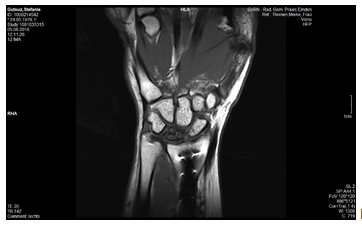

Eine MRT-Kontrolle im Februar 2017 zeigte eine Progredienz, beginnende Fragmentation und Formveränderung des Lunatum, eine neue skapholunäre Dissoziation und zunehmende Gelenkspaltverschmälerung radiokarpal. Ich hatte auch immer noch Schmerzen (genau an gleicher Stelle wie vor der OP aber nicht ganz so schlimm) und die Beweglichkeit war immer noch schlechter als vor der 1. OP.

Anfang Juni 2018 war das MRT, dort zeigte sich eine Höhenminderung des Lunatum. Es war also soweit für OP Nr. 4?! Ich fuhr wieder zum Handchirurgen, seine Oberärztin war anstelle von ihm da und sagte, es müsse nun operiert werden. Ich fragte, ob man es nicht noch verschieben könne (bis ich wieder Anspruch auf Krankengeld hätte und mein Arbeitgeber eine Vertretung für mich). Sie riet dringend davon ab, also bekam ich einen OP-Termin 3 Wochen später. 2 Tage vor dem Termin wurde mir zugetragen, dass dieser Handchirurg fast 40 Klagen anhängig hätte, da habe ich meinen Termin lieber doch abgesagt und mir wieder einen vorstationären Termin in Bad Neustadt geholt (5 Wochen später war der erste frei), da dies ja die Klinik war, die mir zwei Jahre zuvor besonders empfohlen worden war und mir die Lust auf Experimente vergangen war.